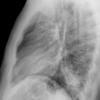

Case 2  Lingular pneum Lat

Date: 04/17/2005

Views: 7042